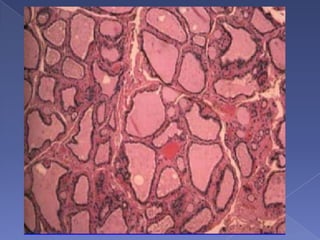

Follicular CarcinomaPathology: round, encapsulated, cystic changes, fibrosis, hemorrhages. Microscopically, neoplastic follicular cells.Differentiated from follicular adenomas by the presence of capsule invasion, vascular invasion.Cannot reliably diagnose basedon FNA.

Follicular CarcinomaPathology: round,encapsulated, cystic changes, fibrosis, hemorrhages. Microscopically, neoplastic follicular cells.Differentiated from follicular adenomas by the presence of capsule invasion, vascular invasion.Cannot reliably diagnose basedon FNA.